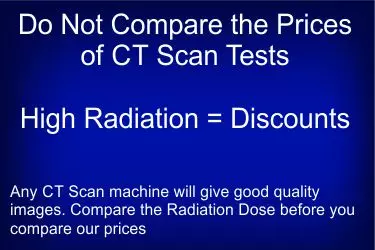

CT Scan of the Chest can be done quite well on all CT Scan machines which are atleast 4 Slices. All our centres have 16 Slice or higher CT Scanners on which CT Scan of the chest can be done in less than one minute. The contrast CT of the chest would take around 30 minutes. The cost of NCCT Chest or HRCT Chest is in the range of Rs. 4500 - 5500 while the cost of CECT Chest is Rs. 6000 - 7000. The cost of kidney function test is in the range of Rs. 500 - 750 which is needed before contrast can be given to the patient. A good CT Scan machine of 50 slices would cost in the range of Rs. 1.5 - 2.0 Crores. Another high cost is the cost of tube which ranges between Rs. 35- 50 lacs and lasts for 3-4 years. The contrast given during the exam is also a very costly consumable. In CECT Chest the cost of the contrast administered is in the range of Rs. 1500 - 2000. We have some of the finest radiologists who are highly trained in CT and MRI reporting. Since the patient has to come in overnight fasting for this test, the appointments are normally given for 9 am in the morning. You can call at +91-8800188335 for booking appointment for CT Scan of the Chest in Gurgaon.